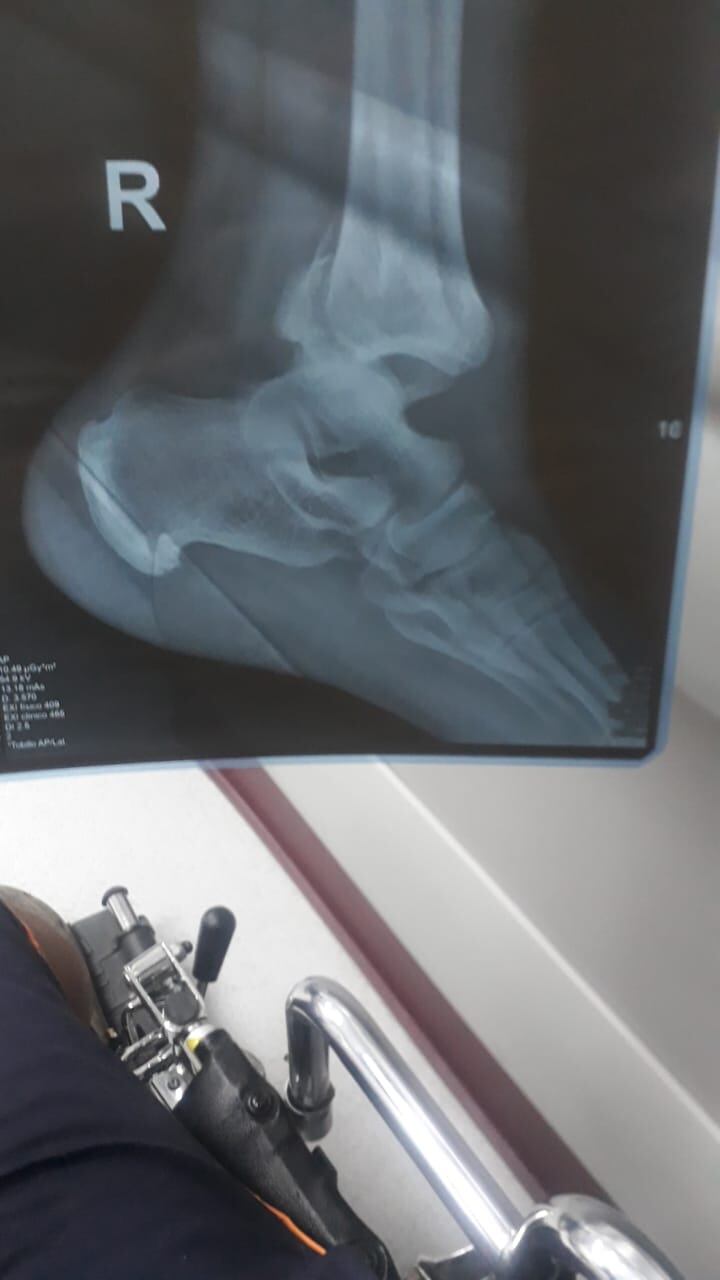

Lo más reciente que le ocurrió fue una caída el 1 de noviembre anterior, cuando se cayó en su casa y se le quebró el tobillo izquierdo.

“Me operaron, me lo quebré en tres partes, me pusieron pines, ahora sí que estoy listo, me golpeé el hombro malo (del brazo derecho donde recibió los balazos) me dijeron que me tienen que poner unas platinas, lo peor es que voy a durar como un mes en reposo.

Afirmó que la dolorosa fractura le ocurrió en su casa cuando pretendía cerrar el portón principal de la casa, pero en ese momento se cayó.

“Sonó como una cáscara de huevo (al referirse del pie)”, manifestó.